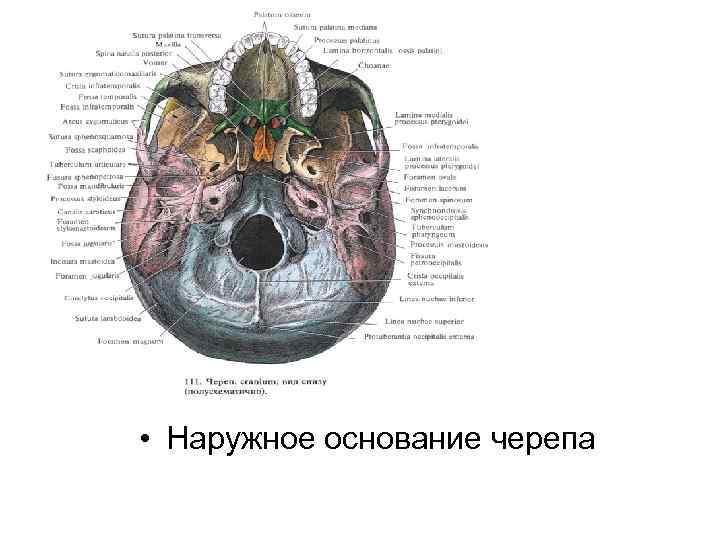

Анатомические детали: Фотографии топографии черепа с нижнего вида

Раздел: Альбом идей